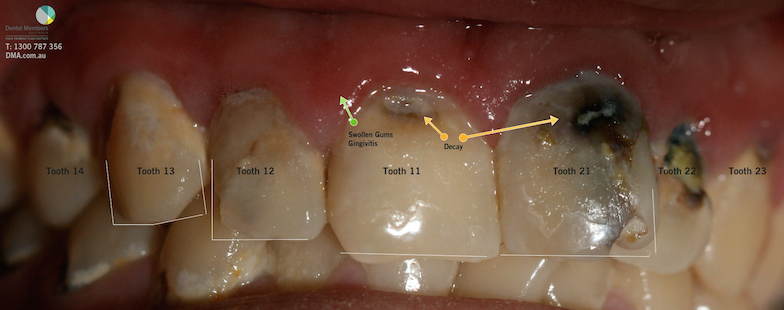

The photo below is a photo of a real patient (32 year old male from Brisbane- Australia) who presented to one of our partner practices with a $2,000 DMA Dental Voucher. He paid $59 per week for 32 weeks to complete treatment.

Composite Filings: (DMA Dentist quoted $450/tooth for the top 7 teeth) .

Gum Disease treatment: Initial evaluation and thorough dental cleaning. ($350)

Total cost of the treating the upper seven teeth and gums using the DMA Voucher was $6,000 or $59/per week.